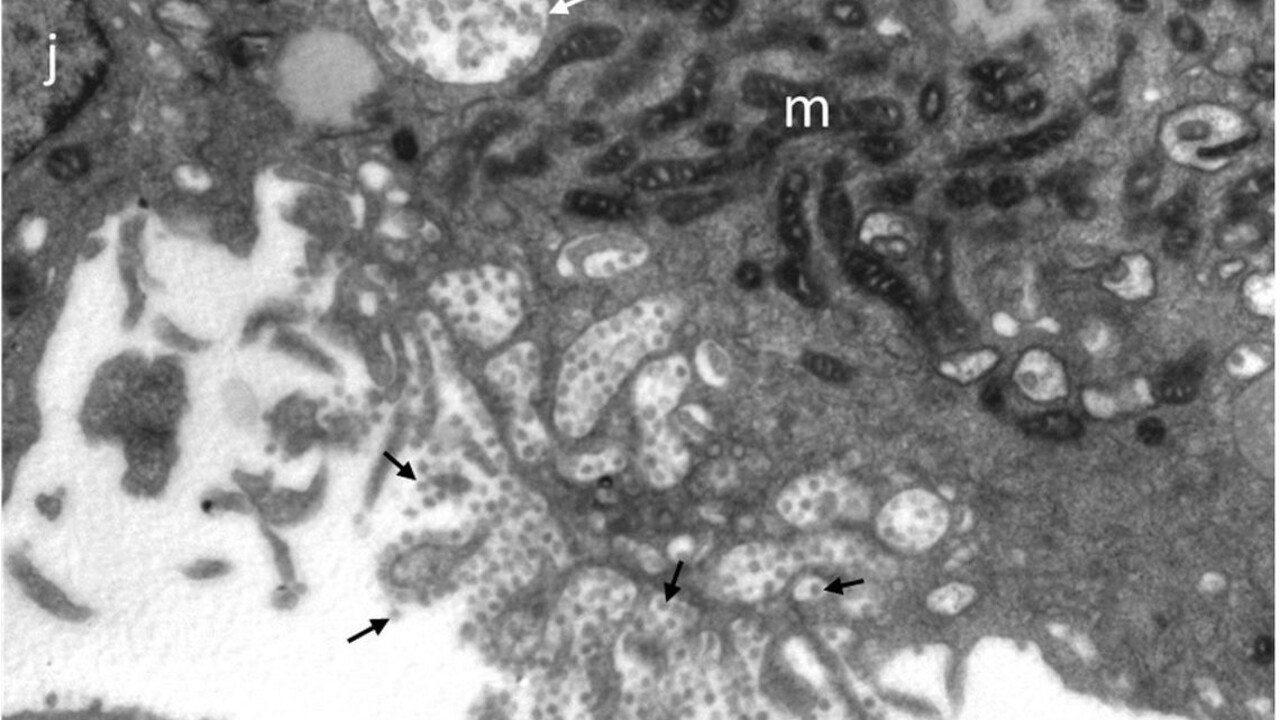

Takto vyzerá "náš" koronavírus. Vedcom zo Slovenskej akadémie vied sa pomocou elektrónovej mikroskopie podarilo vizualizovať vírusové častice koronavírusu SARS-CoV-2, ktoré boli izolované zo slovenských pacientov s Covidom-19. ⁠

Ako uviedla SAV na svojom Facebooku, aj širokej verejnosti sa tak naskytá unikátny pohľad na "slovenský“ vírus, ktorý je už niekoľko mesiacov stredobodom pozornosti našich vedcov. Získané obrazové dáta sa v súčasnosti analyzujú. Cieľom je pochopiť, ako vírus interaguje s infikovanými bunkami hostiteľa.